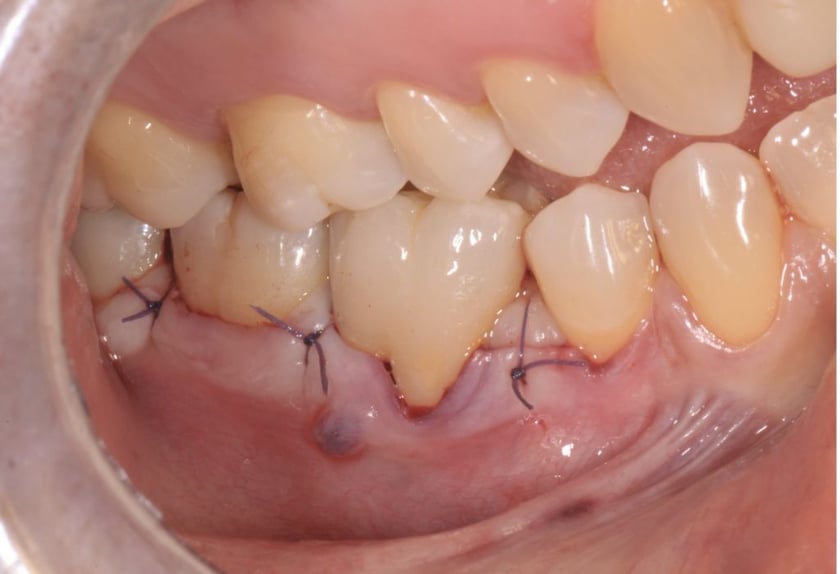

Riparazione chirurgica di estesa perforazione da stripping nella radice mesiale di molare